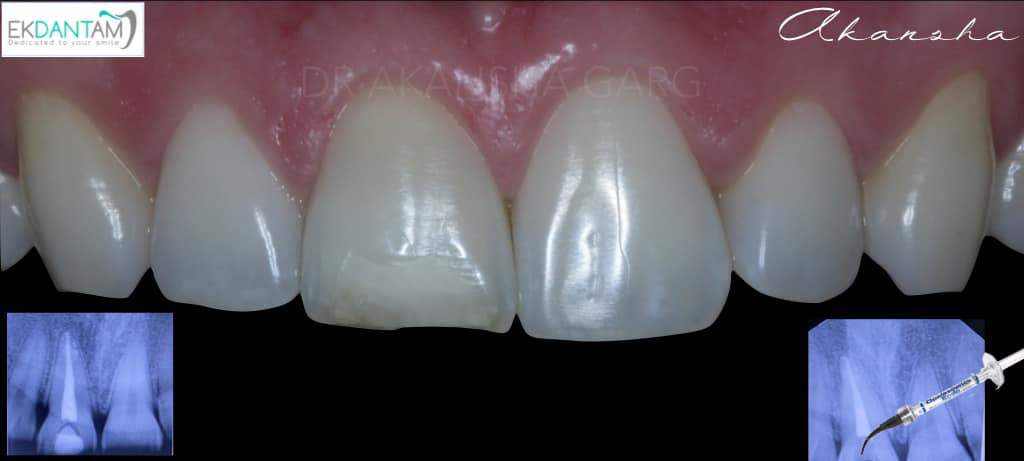

Being gentle to Tooth. It sounds very easy to do subtractive dentistry and grind the tooth and place Crown. The best dentistry is additive dentistry when you save what you have and just replace what’s missing. Case of discoloured tooth due to trauma and Rct years back. Non invasive approach- non vital bleaching followed by composite Incisal edge build up